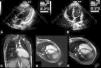

Aos 16 anos, o ecocardiograma mostrava numerosas projeções miocárdicas ecodensas com morfologia em «dentes de serra» na parede inferior, lateral e septo posterior do ventrículo esquerdo (VE), com protusão para a sua cavidade (painéis A e B).

Painel A – ecocardiograma transtorácico bidimensional, projeção apical quatro câmaras modificada, demonstrando projeções miocárdicas ecodensas com morfologia em «dentes de serra».

Painel B – ecocardiograma transtorácico bidimensional, projeção apical quatro câmaras modificada, demonstrando projeções miocárdicas ecodensas com morfologia em «dentes de serra».

Painel C – ressonância magnética cardíaca, eixo longo duas câmaras, demonstrando projeções de miocárdio aparentemente compacto com origem na parede inferior do VE.

Painel D – ressonância magnética cardíaca, corte axial quatro câmaras, demonstrando projeções de miocárdio aparentemente compacto com origem na parede lateral do VE e na face esquerda do septo interventricular.

Painel E – ressonância magnética cardíaca, corte axial quatro câmaras, demonstrando projeções de miocárdio aparentemente compacto com origem na parede lateral do VE e na face esquerda do septo interventricular.

Para melhor esclarecimento morfológico e funcional, o doente foi submetido a ressonância magnética cardíaca. Observaram‐se numerosas projeções de miocárdio aparentemente compacto com origem nas paredes inferior e lateral do VE, e na face esquerda do septo interventricular (painéis C, D e E). Diminuição marginal da função sistólica global, com áreas de hipocinesia de distribuição não coronária, no septo interventricular e ápex do VE. Ausência de realce tardio miocárdico, após administração de gadolínio.